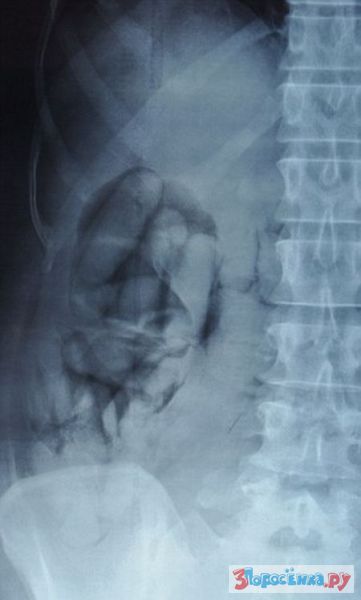

На что только не идут контрабандисты, что бы перевезти запрещенный товар через границу, их бы энергию да в мирных целях...